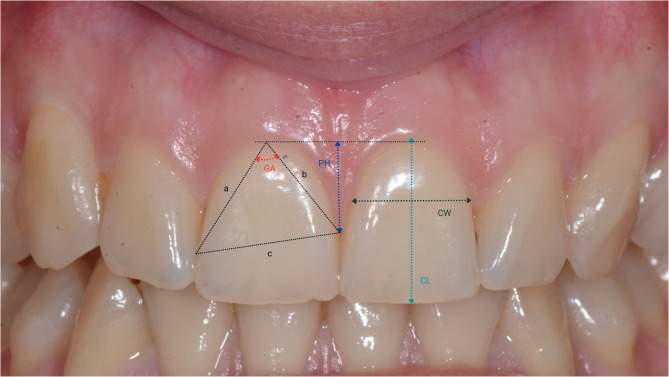

Study models were created by taking alginate impressions of the upper and lower jaws in a stock tray and casting them in Type 3 hard plaster (Durguix, Girona, Spain) according to the manufacturer’s instructions. Casts were measured, and the following parameters (Fig. 3) were recorded:

Fig. 3.

Representation of reference points for measurements of Crown width (CW), Crown length, Papilla height (PH), Gingival angle (GA)

Crown length (CL): the distance between the gingival margin, or, if discernible, the cemento-enamel junction, and the incisal edge of the crown.

Crown width (CW): the distance between the approximal tooth surfaces at the borderline between the cervical (C) and middle (M) portions of the crown, identified after dividing the length of the crown into three equal sections (cervical, middle, incisal).

Papilla Height (PH) was determined by measuring the distance between the zenith of the adjacent teeth and the perpendicular line connecting to the apex of the papilla on the mesial aspect of each tooth.

Gingival Angle (GA): the angle between the two lines that connect the most apical portion of the gingival margin and the most coronal portions of the contact surface.

CL, CW, and PH were measured using a digital caliper (Asimeto, Hong Kong) according to the Olsson et al. [19], and GA was measured using a digital angle gauge (BTS, Ljubljana, Slovenia) with a measurement range of 0-999.9º and a precision of 0.3º. CW/CL ratios were also calculated and recorded for each tooth.